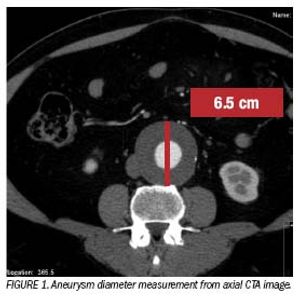

CT angiography of the abdominal aorta is a wellacceptedmodality in the evaluation of bothaneurismal and occlusive disease. In patientswith abdominal aorta aneurysms, it has a major rolein all stages of evaluation.